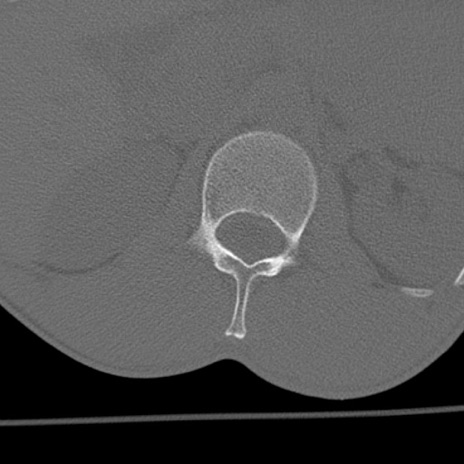

症例3 腰椎CT(横断像)

腰椎CT